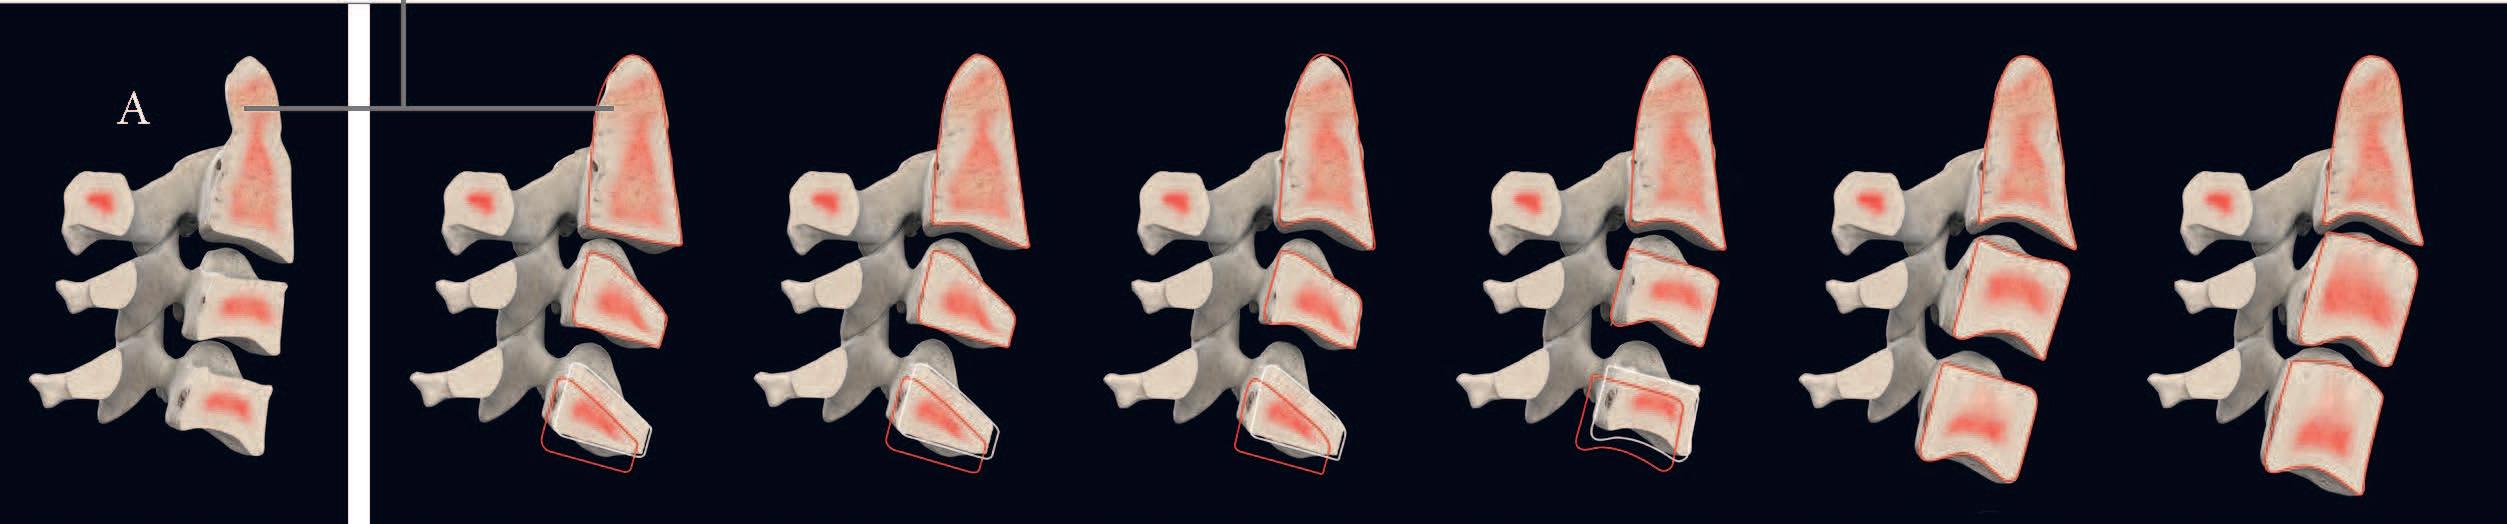

Fig. 57a, b, c > Centri di crescita condilari secondo Petrovic. Le zone dei condili postero-superiori rappresentano centri di crescita attivi della mandibola, ossia centri di sviluppo.

62-68 > Open-bite da abitudine viziata: succhiamento protratto del dito in una bimba di sette anni. Notare bene come il succhiamento protratto del dito determini la spinta indietro della mandibola, l’iposviluppo trasversale del mascellare superiore e, quindi, il conseguente open-bite grave, spesso aggravato anche dall’aumento della divergenza facciale.

69 > Centri di crescita: sono le aree rappresentate in arancione che rappresentano campi di crescita molto attivi, quali le suture craniche e facciali, i condili mandibolari, le tuberosità mascellari, i processi alveolari, le sincondrosi della base cranica. La crescita delle ossa non si verifica tuttavia soltanto in queste zone; tutti campi di crescita interni ed esterni di un osso partecipano di volta in volta al processo.

70, 71 > Centri di Crescita del mascellare superiore: processi di apposizione e di riassorbimento osseo determinano la crescita del mascellare in direzione posteriore.

Contemporaneamente il mascellare superiore viene spostato in avanti.

Nella zona delle giunzioni articolari si origina in tal modo lo spazio necessario per processi di apposizione ossea. Nella dislocazione primaria, il processo di dislocazione si svolge sempre in direzione

opposta al vettore di crescita ossea

(la figura 72

rappresenta siti di crescita cranio/facciale durante la vita dell’individuo.

La 73 rappresenta siti di crescita in corrispondenza del mascellare superiore e della base cranica).